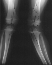

X-Ray Set 3. Post-Op, Neutral alignment